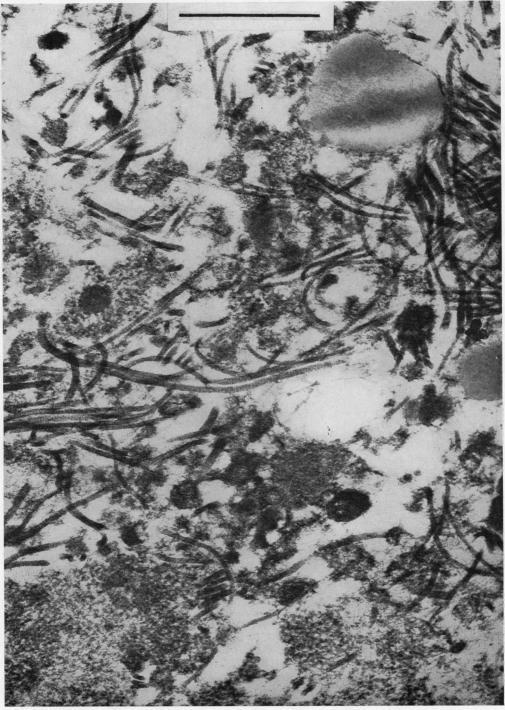

ULTRAMICROSCOPIC STRUCTURE OF THE RHEUMATOID NODULE.

Ann Rheum Dis. 1964 Sep;23(5):345-63. doi: 10.1136/ard.23.5.345.